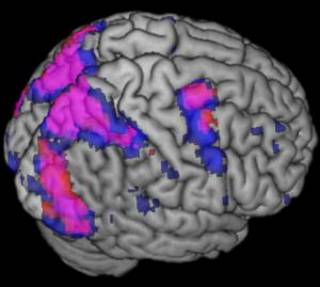

| MIPAV

| MIPAV is a medical image viewer for PET, MRI, CT and microscopy 2D and 3D data-sets. Includes analysis tools to support biomedical data research (Talairach space brain mapping, FRAP, FRET), filtering (spatial, noise, thresholding, Isotropic diffusion), ... Java based cross platform application. Source and binaries available. Funded and developed by the National Institute of Health Center for Information Technology (CIT) Online manual |